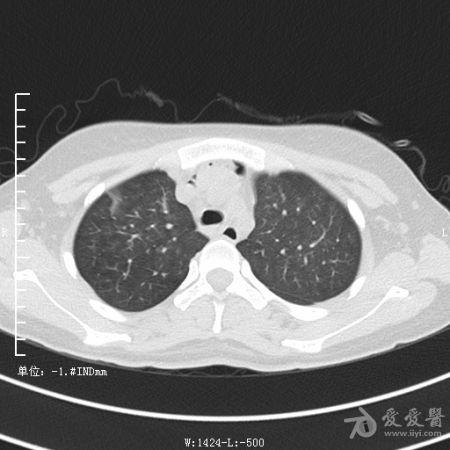

典型支气管扩张及肺水肿CT片

典型支气管扩张肺水肿